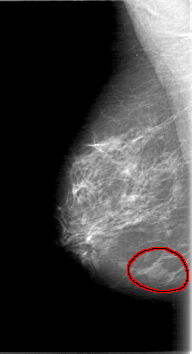

D_4064_1.RIGHT_MLO

FILE: D_4064_1.RIGHT_MLO.OVERLAY

TOTAL_ABNORMALITIES 1

ABNORMALITY 1

LESION_TYPE MASS SHAPE LOBULATED MARGINS ILL_DEFINED

ASSESSMENT 0

SUBTLETY 5

PATHOLOGY BENIGN

TOTAL_OUTLINES 1

BOUNDARY